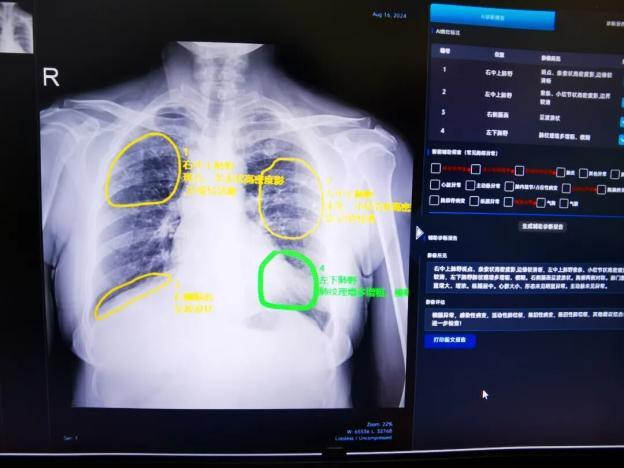

所(院)医务人员正通过“AI肺结核影像智能辅助诊断系统”复核疑似活动性肺结核病例的影像资料

“AI肺结核影像智能辅助诊断系统”对活动性肺结核病例的影像资料进行智能辅助诊断

自2024年5月搭建“AI肺结核影像智能辅助诊断系统”以来,该系统目前已覆盖10余家二级医院、疾控中心等基层机构,累计接收并AI诊断胸片数据122800余张,筛选出活动性肺结核病历2400余例,有效推动全省结核病筛查实现同质化、标准化,显著提升了基层医疗机构的筛查和诊断能力。